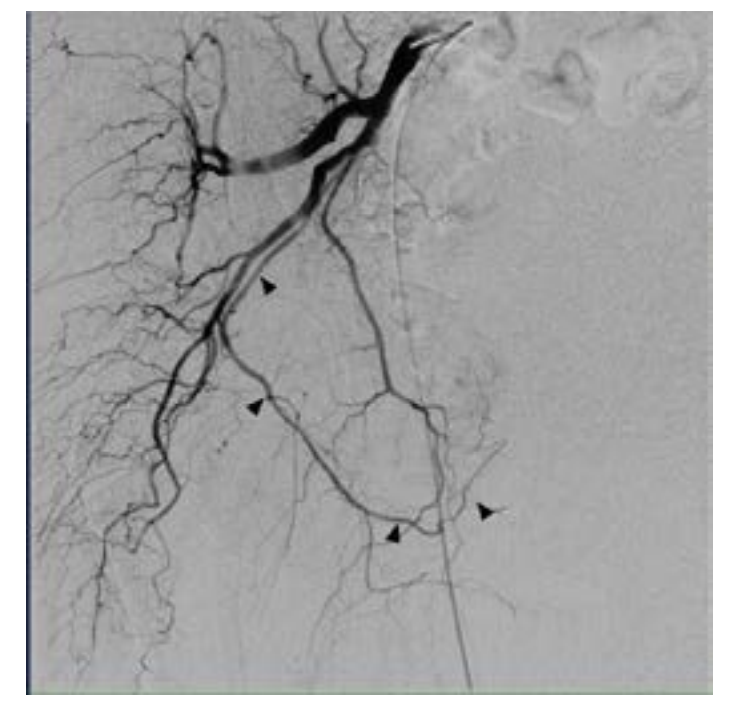

A 74-year-old male with past medical history of hypertension, coronary artery disease, and BPH with LUTS refractory to medical management presented for evaluation. The patient underwent an MRI of the prostate demonstrating a 182 cc gland with an enlarged transitional zone measuring 144 cc (Figure 1). The patient’s baseline IPSS and QoL were 18 and 5, respectively. Given the patient’s prostate gland size, and medical comorbidities, he elected to undergo PAE for management of his LUTS. On the day of his PAE, right common femoral arterial access was obtained and a pigtail DSA was obtained delineating pelvic arterial anatomy. On the right, the prostatic artery arose from a vesiculoprostatic trunk, with a shared origin with the superior vesicular artery (Figure 2). This was selectively catheterized with a progreat alpha microcatheter (Terumo, Tokyo, Japan), and 016” fathom microwire (Boston Scientific, Marlborough, MA). Angiography demonstrated perfusion of the entire right portion of the gland, without evidence of extra-prostatic supply (Figure 3). Embolization was performed with 300-500 micron Embospheres (Merit Medical, South Jordan, UT) to stasis. On the left, the prostatic artery arose from the left obturator artery (Figure 4). This was subsequently catheterized with the same catheter/wire combination, with angiography demonstrating left glandular perfusion without extra-prostatic supply (Figure 5). Embolization was again performed to stasis with 300-500 micron Embospheres. The patient did well post-procedurally with self-limited urinary frequency and dysuria for 3 days. By 3 months post PAE, the patient reported a significant improvement in his LUTS, with an IPSS/QoL of 3 and 0, respectively.

Initial arterial access was obtained and a pigtail catheter was advanced into the abdominal aorta to the level of the aortic bifurcation. Using a hybrid angio-CT unit (Nexaris, Siemens Healthcare AG, Forchheim, Germany), a CTA was obtained to delineate arterial anatomy and determine the pattern of glandular reperfusion. Multiplanar reconstruction was performed using syngo DynaCT and Embolization Guidance software (Siemens Healthcare AG, Forchheim, Germany). These images demonstrated no perfusion from either the previously treated right or left prostatic arteries, which now appeared markedly attenuated. Instead, the majority of the gland had been revascularized through a distal internal pudendal artery collateral on the right, with more proximal branches perfusing the cavernosal tissues (Figure 7). These cavernosal branches also appeared to be the sole supply to the cavernosal tissues on the right, and therefore critical to avoid nontarget embolization to penile tissues. The CTA/Embolization Guidance data sets were then fused to create an overlay of the vessel trajectory to be displayed during 2D fluoroscopy. Given the vessel tortuosity and small caliber size (Figure 8), an Excelsior SL-10 microcatheter (Stryker, Fremont, CA) and 014’ Synchrosoft microwire (Stryker) were used to select the terminal branch of the internal pudendal artery distal to the cavernosal branches. Angiography from this location demonstrated brisk antegrade flow with perfusion of the central gland without extra-prostatic perfusion (Figure 9). Embolization was performed to stasis using 300-500 micron particles. Completion angiography demonstrated no further prostatic perfusion and preservation of more proximal cavernosal branches. The patient had an uneventful postoperative course, and by 1 month post PAE his IPSS/QoL was 3/0, respectively.